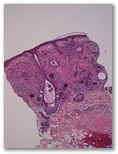

Placa umbilicada en cara

1. Triquilemoma

2. Siringoma

3. Basocelular morfeiforme

4. Otro dx